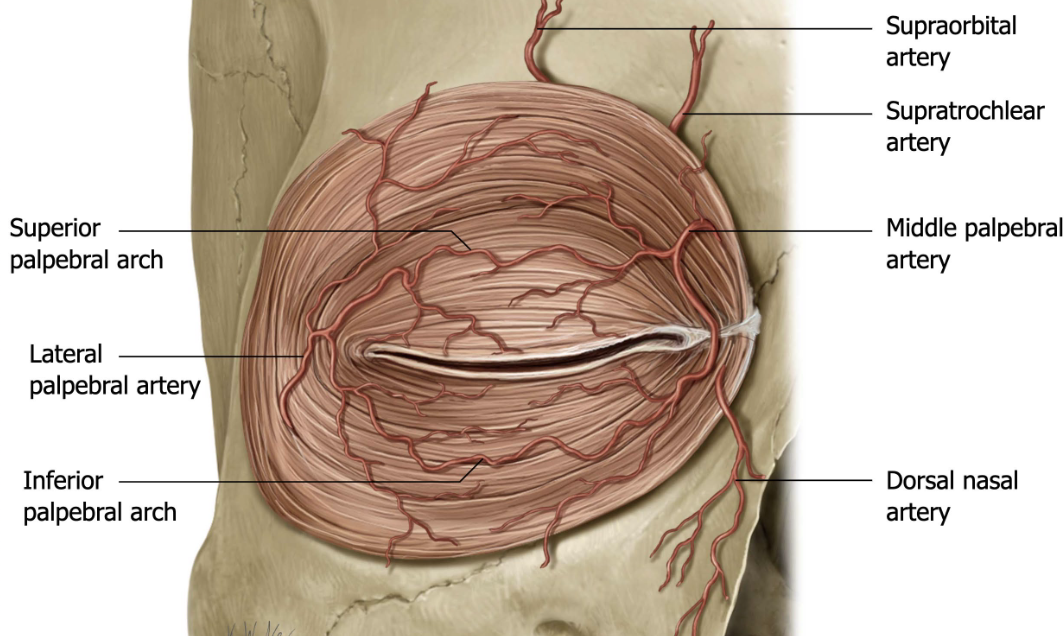

Define arcade.

connective networks of vessels that allow for constant blood flow with movement

Describe the Arterial Supply of the Eyelids.

eyelids are richly vascularized

Main supply: Vascular arcades formed by the medial & lateral palpebral branches of the ophthalmic artery

Upper lid: 2 arcades

Lower lid: 1 arcade

Additional supply: Branches from the infraorbital, facial, transverse facial, and superficial temporal arteries